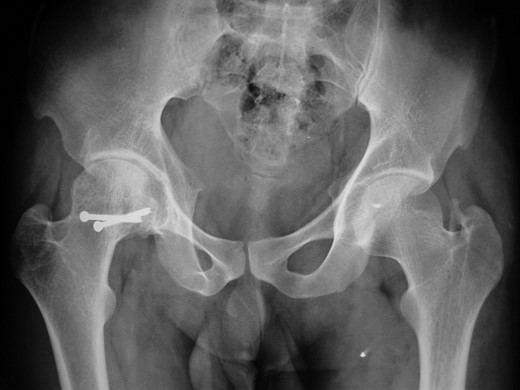

At 1- and 7-year follow-up, X-rays were satisfactory with no signs of osteonecrosis of femoral head (Figs 7 and 8). Nail from the left femur and right distal femoral plate were removed at the end of 2 years. The patient at 7 years post-surgery had a good functional assessment (Friedman and Wyman) score with X-ray bearing no signs of avascular necrosis or heterotrophic ossification, and the fracture had united. Over 7 years, patient who is a student by profession is bearing full weight and is successfully performing his personal and social duties. The active range of motion at right hip was 0–110° flexion and 0–10° extension, external rotation 0–30° with internal rotation 0–10° with slight loss of terminal abduction (Figs 9 and 10).